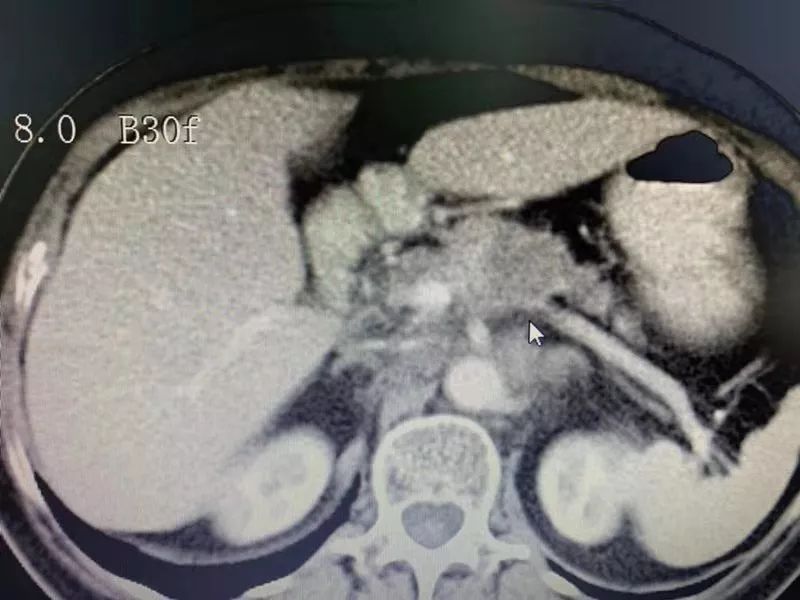

手术前

手术后

相比其它的热消融手术,热消融会把组织纤维架构全部打死,敌我不分,打死之后,有个坏死区始终存在,很少有连坏死区都消失的情况。

而纳米刀对正常的纤维架构影响很小,正常组织会吸收,再生,所以成女士才会出现这样出乎意料的疗效。